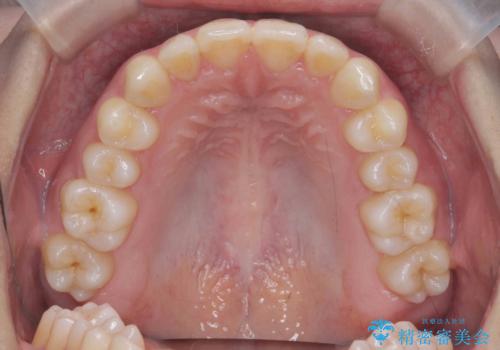

ガタつきの改善 マウスピース矯正治療

- 歯のがたつきの改善を求めて、矯正治療を希望され来院されました。

少量の歯のディスキング、歯列弓拡大、アタッチメントを装着することで審美的な歯列へとマウスピース矯正インビザラインを用いて治療を行います。

マウスピース矯正は装着時間の遵守が非常に大切ですが、しっかりと20時間/日以上の装着を守っていただいたおかげで良好な治療結果を得ることができました。